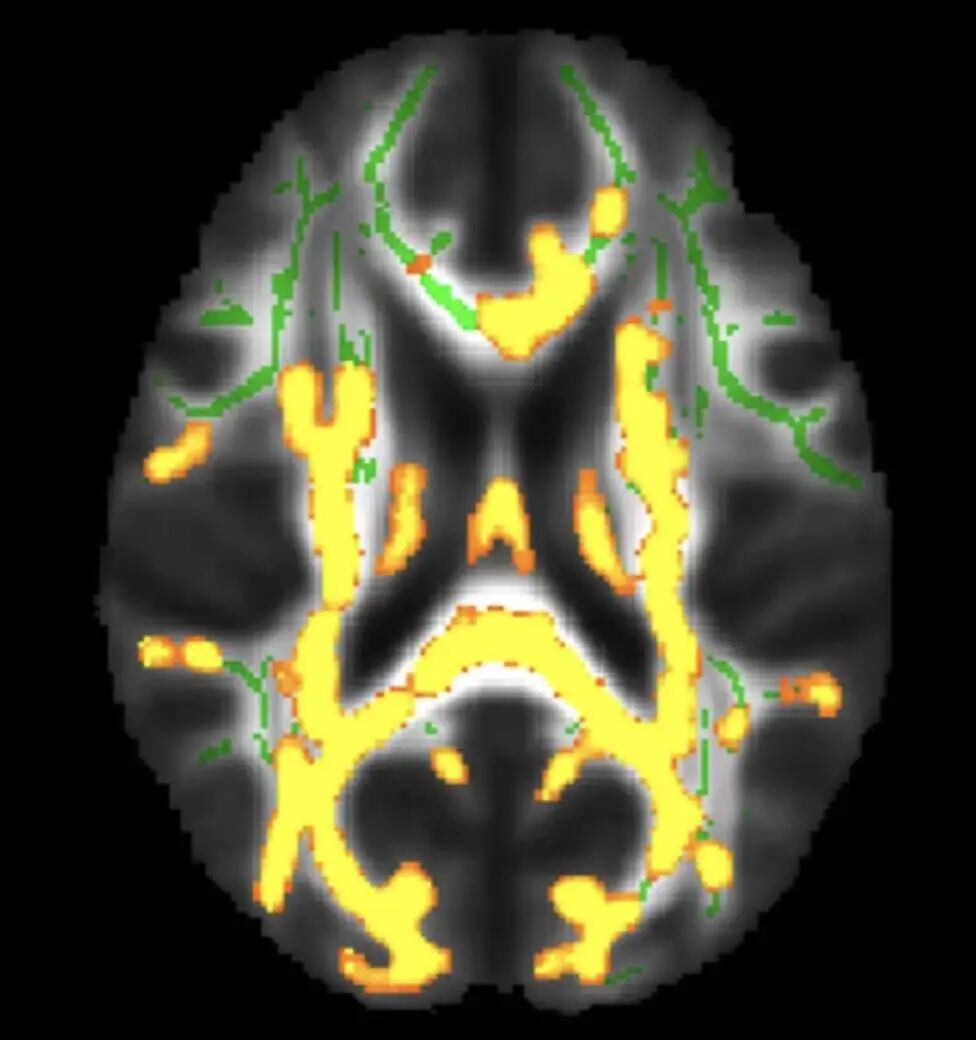

脑部扫描显示隐藏的内脏脂肪水平较高,神经炎症(黄色)增加

有研究发现,认知正常的中年人中,内脏脂肪更高的人,大脑区域(右侧楔前叶皮质)中的淀粉样蛋白更多。而后者,正是阿尔兹海默症的早期信号之一。